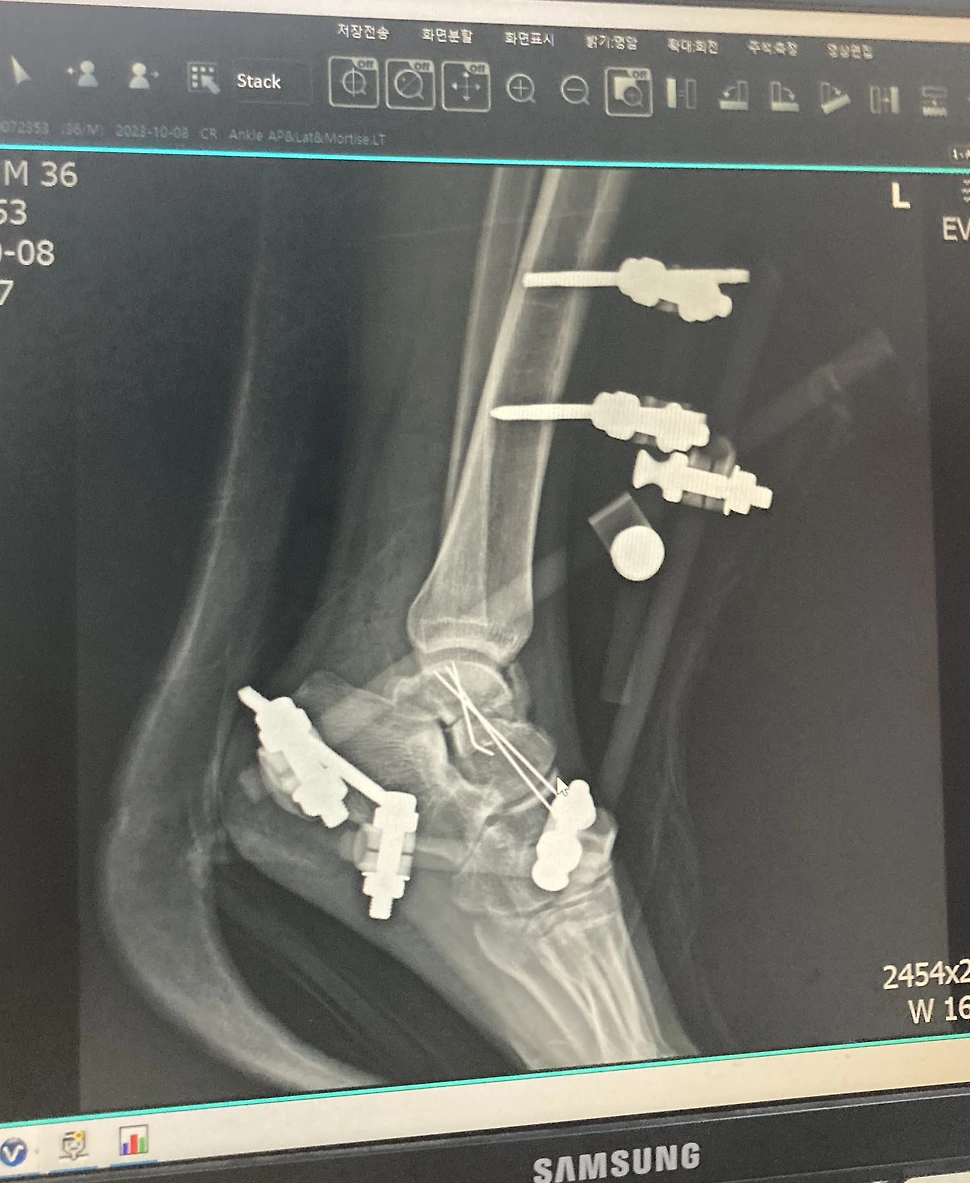

수술 들어가기 전 간단한 설명을 해주시긴 하셨는데 어려운 용어가 있어서 잘 이해는 가지 않았다. K강선을 이용해서 부러진 뼈가 움직이지 않게 고정한다고 간단하게 이해를 했다. 수술실에 들어서자 차가운 공기가 느껴졌다. 왠지 모르게 수술실의 분위기가 싫었다. 수술 침대에 눕고 마취과 선생님이 오시더니 내 등을 새우처럼 굽히게 하고 옆으로 눕게 했다. 척추마취였다. 척추가 딱금 거리더니 허리 밑 부분의 감각이 사라졌다. 허리 밑 부분은 바늘로 찔러도 느낌이 없었다. 그리곤 곧 잠이 들었다. 수술은 6시간 정도진행 되었다.

수술 후 의식이 돌아온 나는 깜짝 놀랄 수밖에 없었다. 철제 봉과 나사들이 내 다리에 박혀 있었다. 수술 중 의식이 없어 무슨 일이 일어났는지 모르니 더욱 두려운 감정이 밀려왔다. 미리 설명은 들었지만 내 다리에 나사와 철제봉이 박혀있는 것을 직접 보니 만감이 교차했다. 나는 처음 겪는 일에 당황하여 간호사에게 여러 가지를 물어보았다. 수술이 잘 된 건가? 나사를 이렇게 박는 게 맞는 거냐? 등. 간호사는 나를 진정시키며 수술 잘 되었고 의사 선생님이 실력 있는 분이라며 나를 진정시켰다.

의사 선생님은 절대로 발을 땅에 디디면 안 된다는 처방을 내리셨다. 응급수술이기 때문에 완벽하게 고정되어있지 않아서 발을 디디면 큰일 날 수 있다고 하셨다. 그리곤 부기가 빠져야 본 수수술을 할 수 있다고 하셨다. 본 수술은 부러진 뼈에 나사를 박아서 뼈가 붙을 때까지 고정하는 수술이다. 이 수술은 발을 절개해서 열어야 하는데 수술 부위가 많이 부어 있으면 수술이 어렵다고 하셨다. 기약 없이 부기가 빠지기를 기다리며 산송장처럼 병원에서 누워 지내야 했다.

정확한 병명은 거골의 폐쇄성 분쇄골절이다. 그 당시 의사 선생님 의견으로는 다 나아도 반드시 절뚝거릴 것이라고 하셨다. 그리고 거골이라는 부위가 연골로 둘러 쌓여있어 골절 시 연골 손상도 동반할 것이고, 특히 피가 잘 안 통해 벼가 잘 붙지 않고 함몰될 수 있는 최악의 가능 성도 있다고 하셨다.